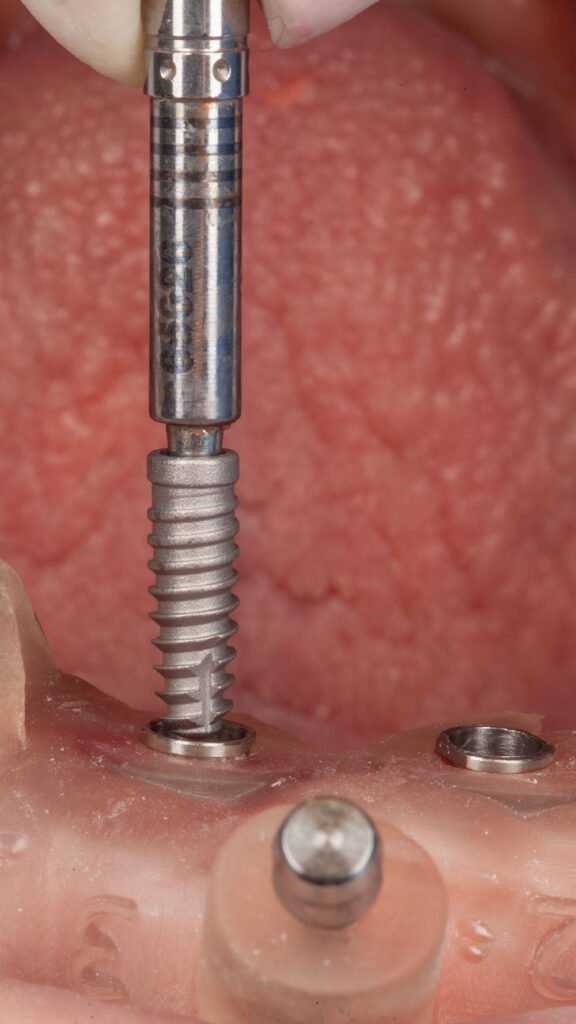

Instalação dos implantes com o guia cirúrgico em posição.

Momento logo após a confecção dos implantes guiados superiores.